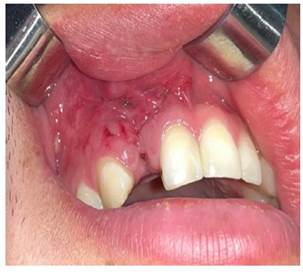

Se le realizó el control postoperatorio a los 7 días, donde se observó cicatrización satisfactoria, se retiraron los puntos de sutura y se realizó una rehabilitación provisional; posteriormente está planificada la rehabilitación con implantes (Figura 7a y 7b).